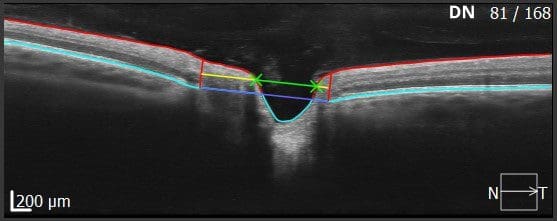

In Abbildung 5 sind die Markierungen in den verschiedenen Schichten zur Berechnung der Cup-Disc eingezeichnet. Sowohl für die Werte der Nervenfaserschichtdicke als auch für die Ergebnisse der Cup-Disc-Statistik können deutliche Abweichungen zur Norm vorhanden sein, ohne dass es sich dabei um krankhafte Veränderungen handelt. Der exakte Winkel, in dem die Nervenfasern aus der Papille austreten, können deutlich variieren. Auch die Größe der Disc und Cup können ganz individuelle Werte annehmen, ohne sofort als pathologisch zu gelten. Insbesondere die Fehlsichtigkeit des Kunden muss an dieser Stelle als beeinflussender Parameter betrachtet werden.